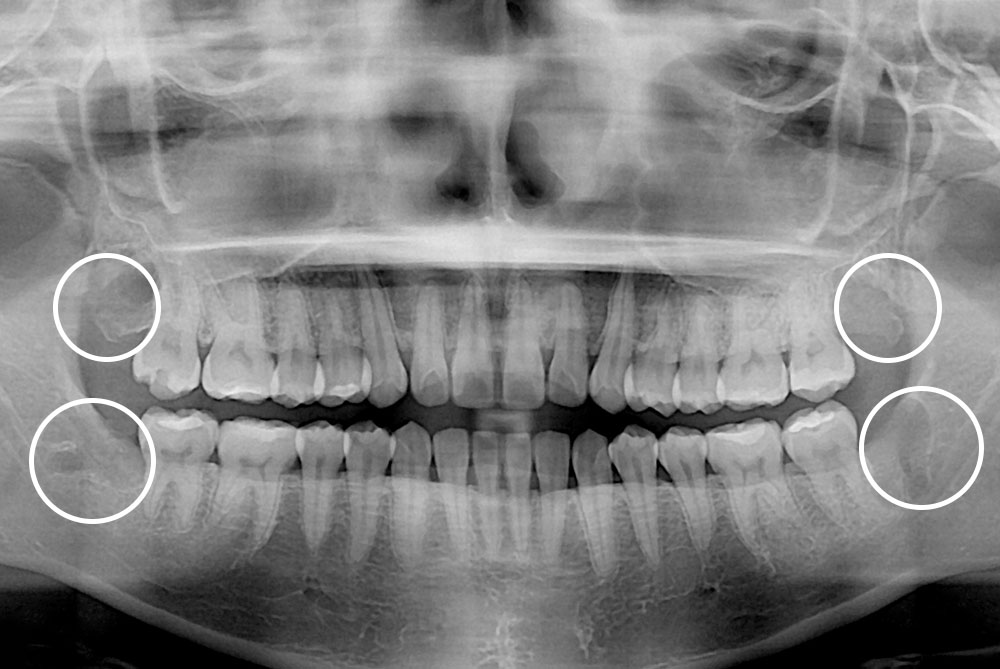

[사랑니] 매복 사랑니 발치

치료전 : 2019-04-01